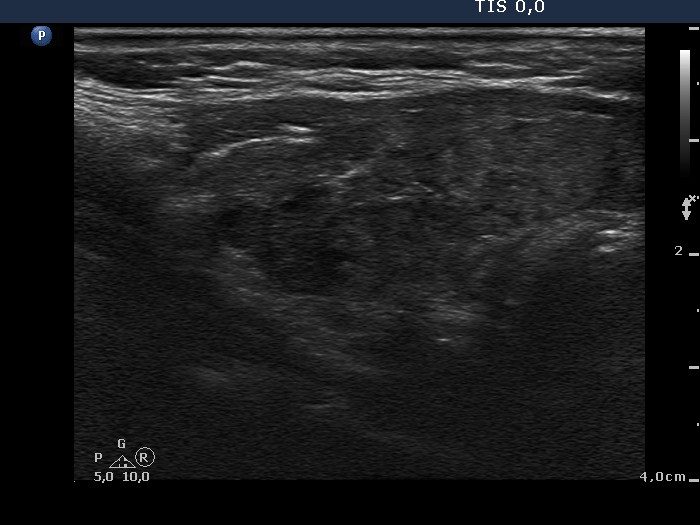

Case 739

Follow-up investigation two years later (ultrasonographic picture 2)

Right lobe, longitudinal scan.